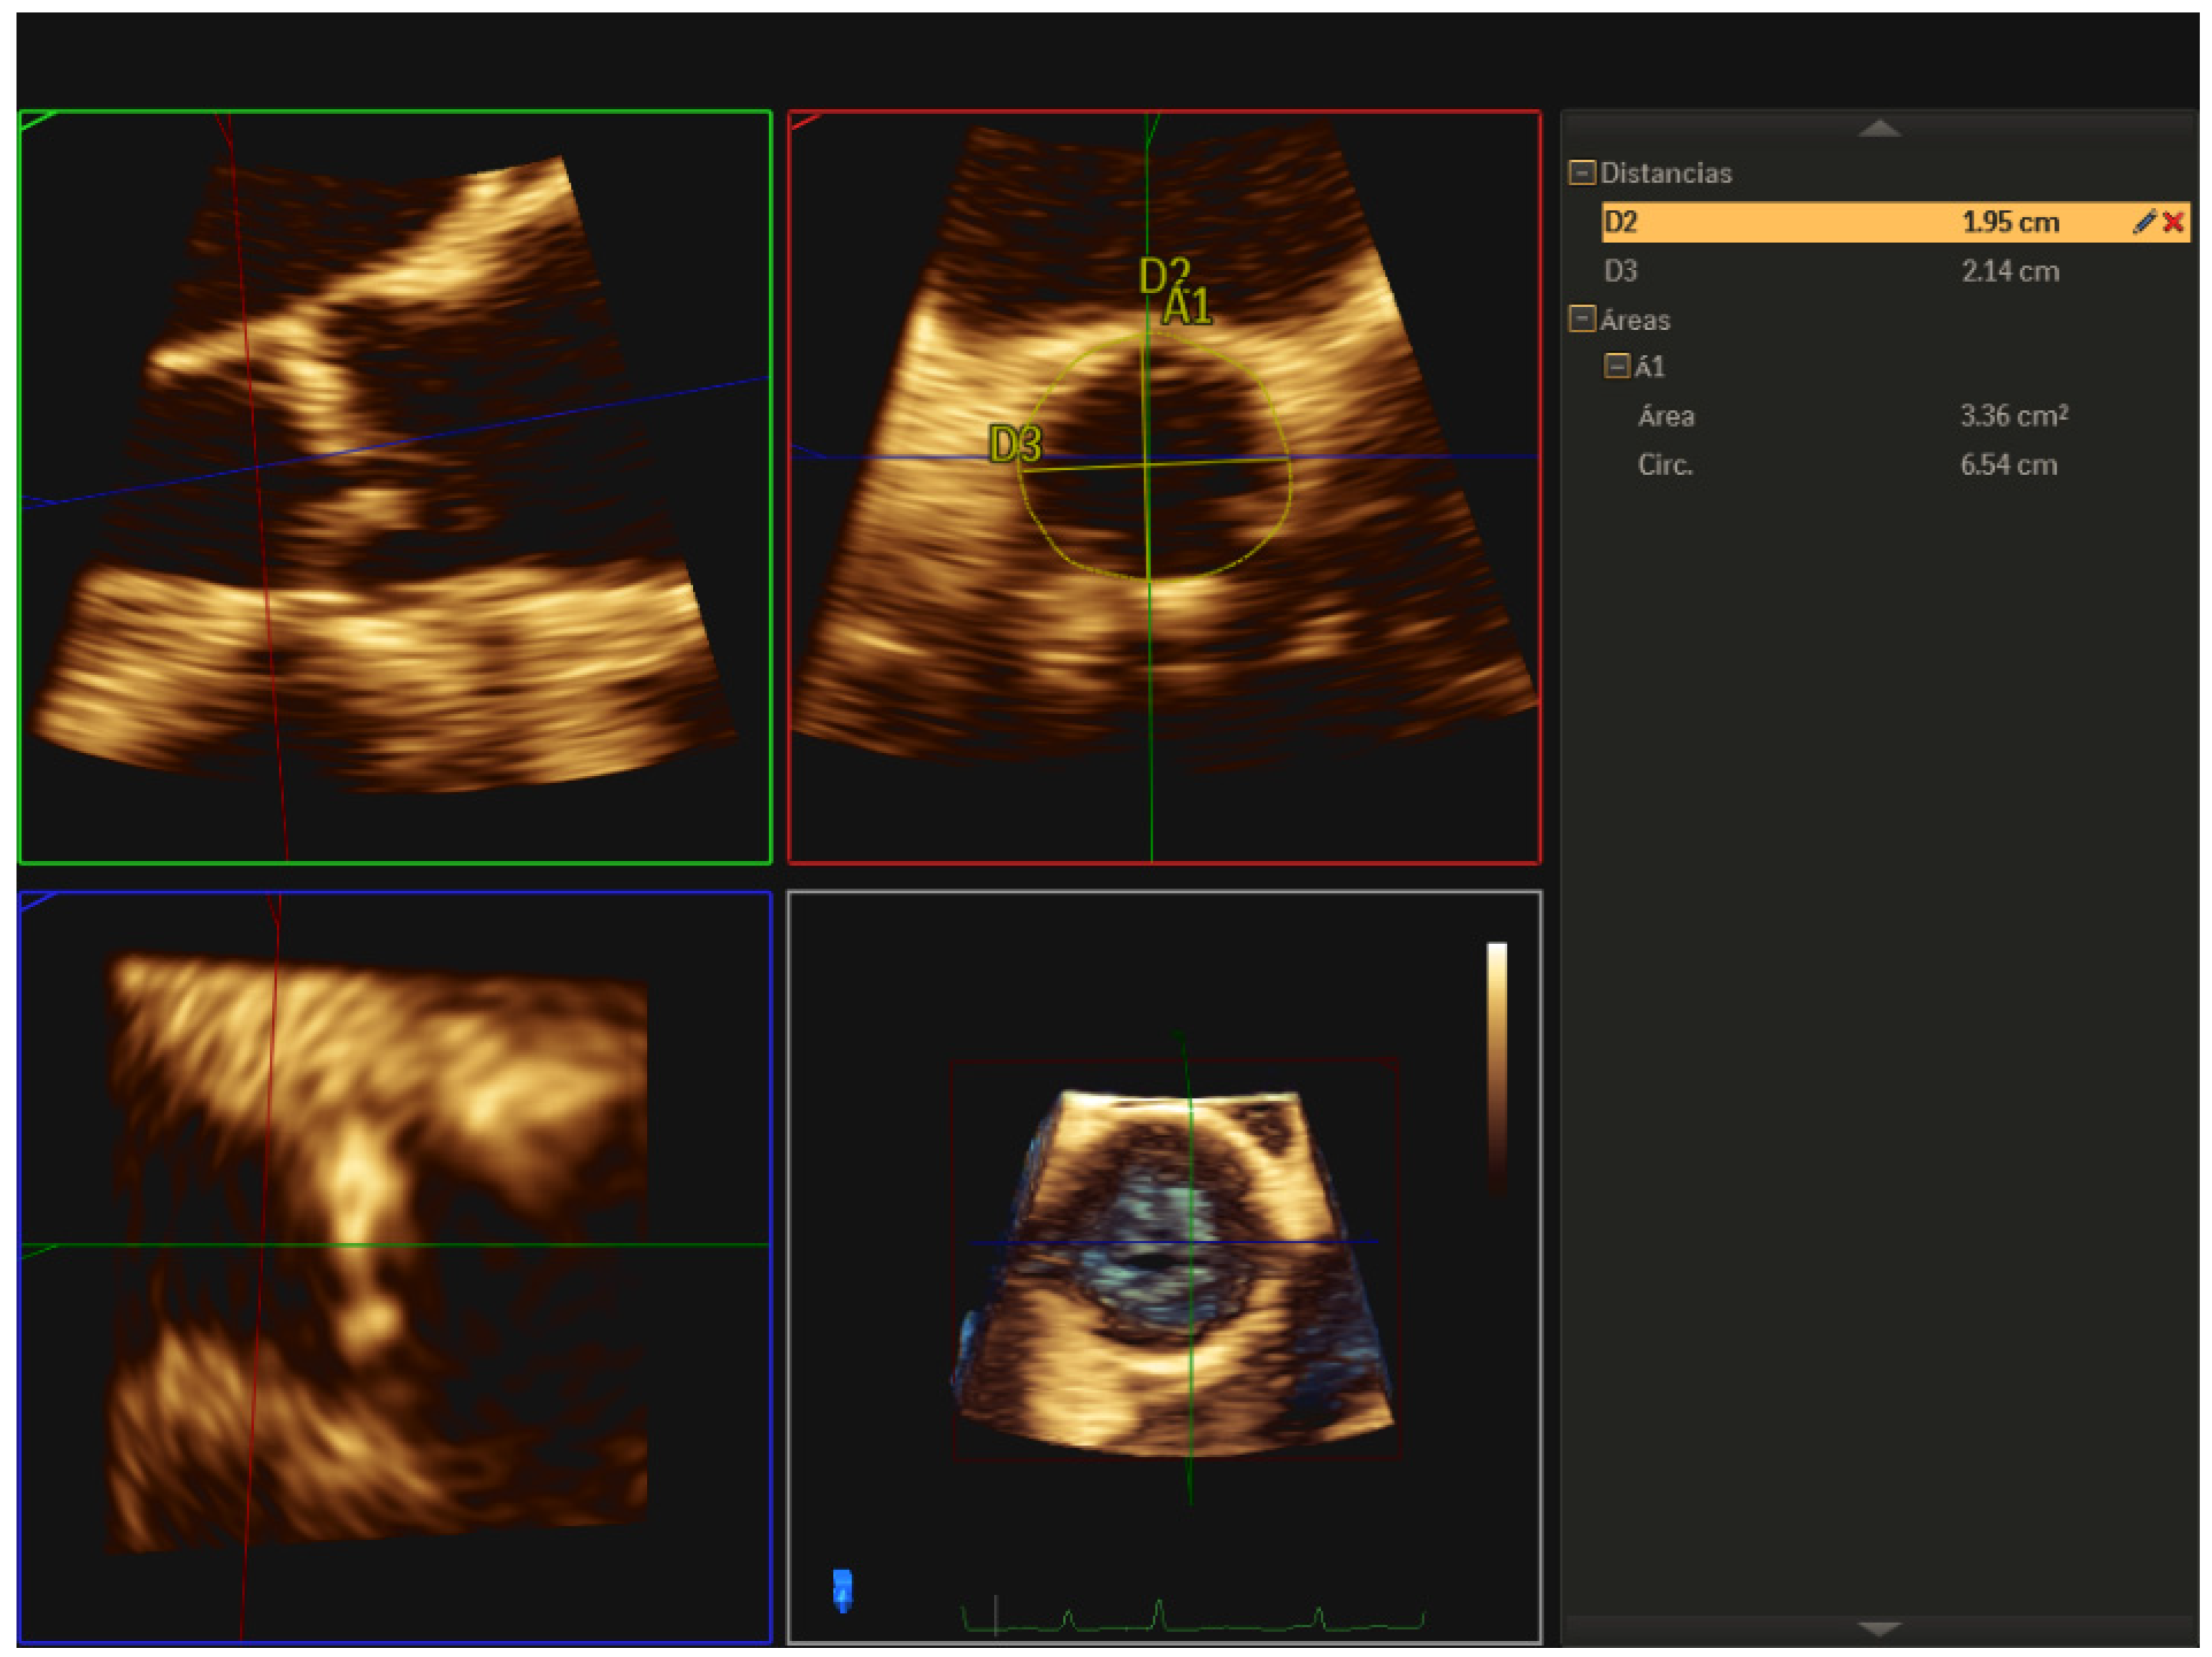

| 1 | Three-dimensional TEE allows us to accurately evaluate the aortic valve morphology and measure the valve annulus prior to TAVR implantation, helping us to choose the appropriate size of the prosthesis, especially useful in cases where the cardio-CT is not of adequate quality. |

| 3 | Three-dimensional TEE is the best technique to detect and quantify perivalvular regurgitation after TAVR implantation, a fundamental aspect in deciding whether immediate valve postdilation is needed or not. |